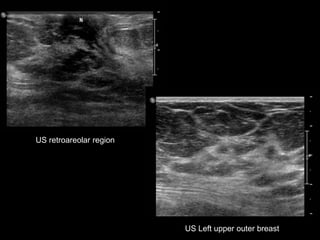

US retroareolar region

US Left upper outer breast

• What are the findings?

• What would you do next?

• What is your differential diagnosis?

• What are your recommendations?